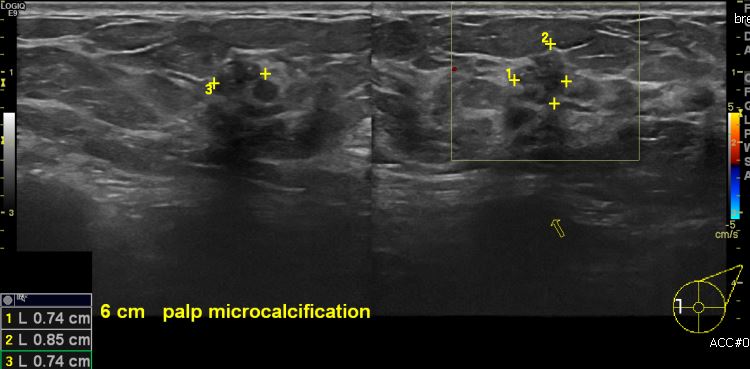

상기환자 건강검진상 이상소견으로 내원하신 50대 여성분으로  좌측 9시 방향에서 6cm

떨어진 거리의 만져지는 멍울 조직검사 시행하여 좌측 유관암 진단되었습니다.